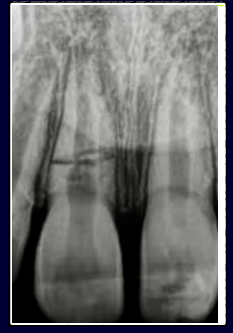

avulsion

-tooth completely out of socket

-unknown variables

-pulp necrosis, ankylosis, root resorption concerns

ankylosis following avulsion

-directly related to the damage of the PDL

replantation after avulsion

-extra-oral dry time <20 minutes

-critical to replant tooth into socket ASAP (doesn’t realistically happen)

-storage medium: saline, milk, saliva

-flexible splint 1-2 weeks

-may minimize ankylosis

avulsion in young permanent teeth

-replant and observe

-open apex = chance for revascularization to occur

avulsion with mature root

-replant, immobilize with flexible splint, then initiate RCT one week later

avulsion treatment goals

-preserve the PDL FIRST (minimizes resorption)

-then treat pulp

avulsion treatment

-initiate RCT one week later

-place calcium hydroxide (pH 12.4)

-calcium hydroxide alters the pH of the external root surface and may necrose the PDL fibers trying to re-attach themselves

-RCT one week later (fate of PDL decided in the first week after avulsion)

-minimum 1 week to 6 months in calcium hydroxide